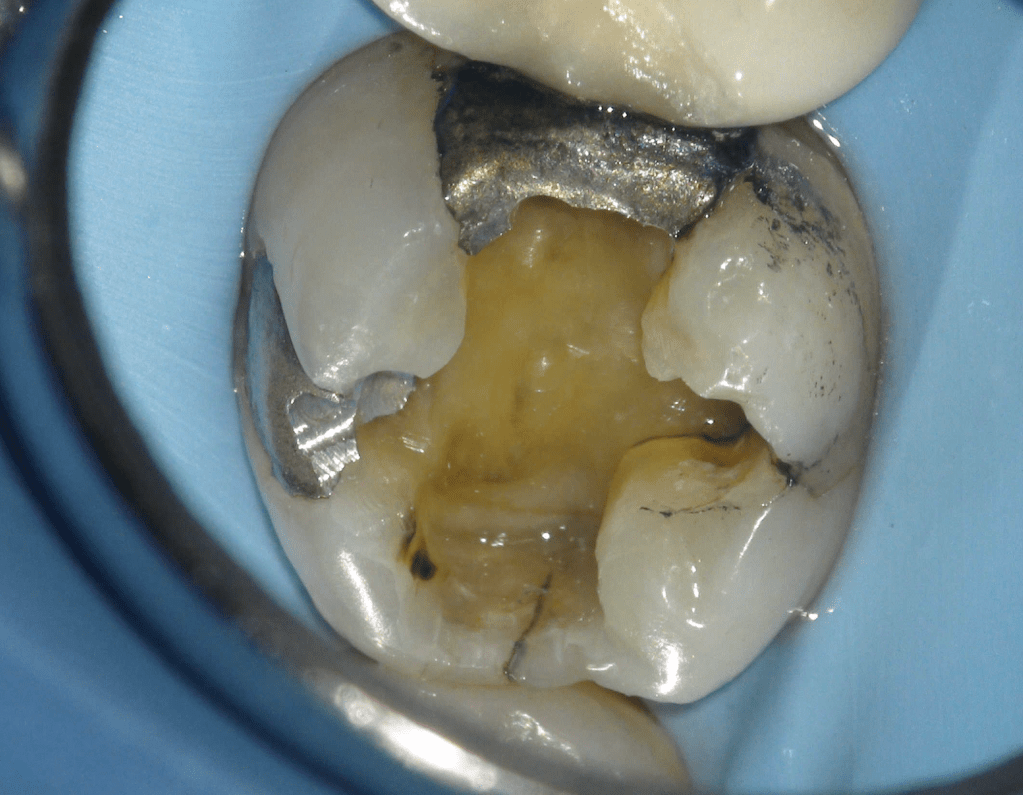

Fisura, remoción amalgama para explorar